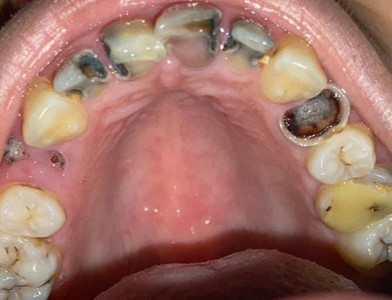

Endodontics

Before After

Before

After

Root canal treatment with crown restoration